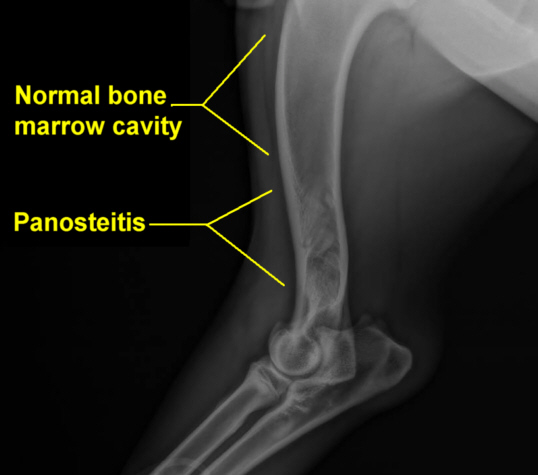

4. Ruger has Panosteitis again. I had no idea what that was, so besides what the vet told me, I did some web browsing and educating myself about it. It is a painful inflammation of the bone that causes limping (temporary pain/limping - it's like growing pains). He has had it two other times, but I think this time was the worst. He wasn't even walking on his front right leg it hurt so bad, so basically he was walking on three legs everywhere. The vet prescribed pills to bring down the inflammation but after giving one to him (even with food) he got sick. As in throw up sick. The rest of the evening he laid with his head on either Aaron or my lap and he looked so sad and in pain. We really felt bad for our boy. I can already tell today, though, that he is feeling better.